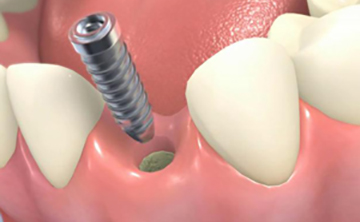

インプラントの構造は、上部構造・アバットメント部(支台部)・歯根部の3つの構造から成り立っています。

歯根部は、チタン製で、この部分と顎の骨が結合します。

インプラント歯根部のチタンが骨と結合する確率は、95%と高い確率となっています。

歯科用インプラントはチタン製です。

チタンは生体親和性が高く発がん性もないためインプラントの素材は大変安全なものです。

血液の中でも腐食を起こさず超長期的に体内で機能できるものを選んでおりますのでご安心ください。